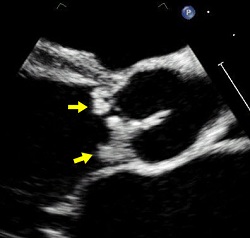

½É³»¸·¿° ȯÀÚÀÇ ½ÉÀåÆÇ¸·¿¡ Ç÷Àü, ¼¼±Õµ¢¾î¸® µîÀÌ Çü¼ºµÈ ½ÉÀåÃÊÀ½ÆÄ »çÁø | Áö±Ý±îÁö ½É³»¸·¿° Ä¡·á´Â 4ÁÖ ³»¿ÜÀÇ Ç×»ýÁ¦ Áֻ縦 ÅëÇØ ¿øÀÎÀÌ µÇ´Â ¼¼±ÕÀ» Á¦°ÅÇϰí ÀÌÈÄ »óȲ¿¡ µû¶ó ¼ö¼úÀ» ÇÏ´Â ¹æ½ÄÀ¸·Î ÀÌ·ïÁ³´Ù.